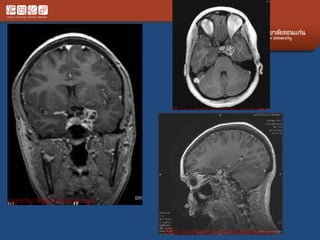

Pituitary Macroadenoma

• Usually soft

• Elevate diaphargma selle

• Often contrasted at diaphargmatic hiatus as

tumor growth into the suprasellar cistern

• Snowman shape

• *commonest large tumor of the skull base